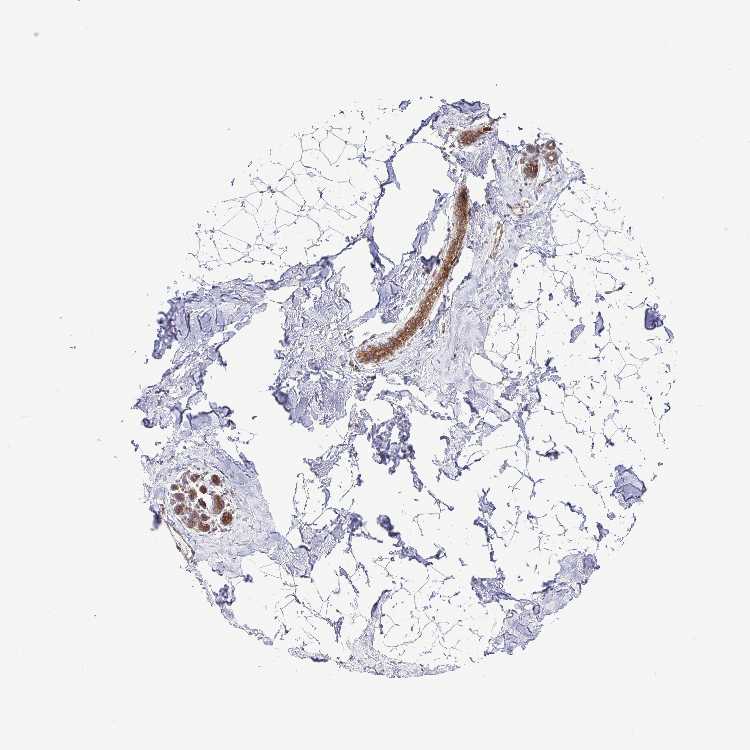

TISSUE PRIMARY DATA BREAST Show tissue menu

BREAST - Antibody stainingi

Antibody staining in the annotated cell types in the current human tissue is reported as not detected, low, medium, or high, based on conventional immunohistochemistry profiling in selected tissues. This score is based on the combination of the staining intensity and fraction of stained cells.

Each image is clickable and will lead to virtual microscopy that enables deeper exploration of all samples and also displays staining intensity scores, fraction scores and subcellular localization as well as patient and tissue information for each sample.

Antibody HPA037589Antibody HPA037590Antibody CAB009846

Adipocytes LowNot detectedNot detected

Glandular cells MediumMediumMedium

Myoepithelial cells MediumMediumMedium